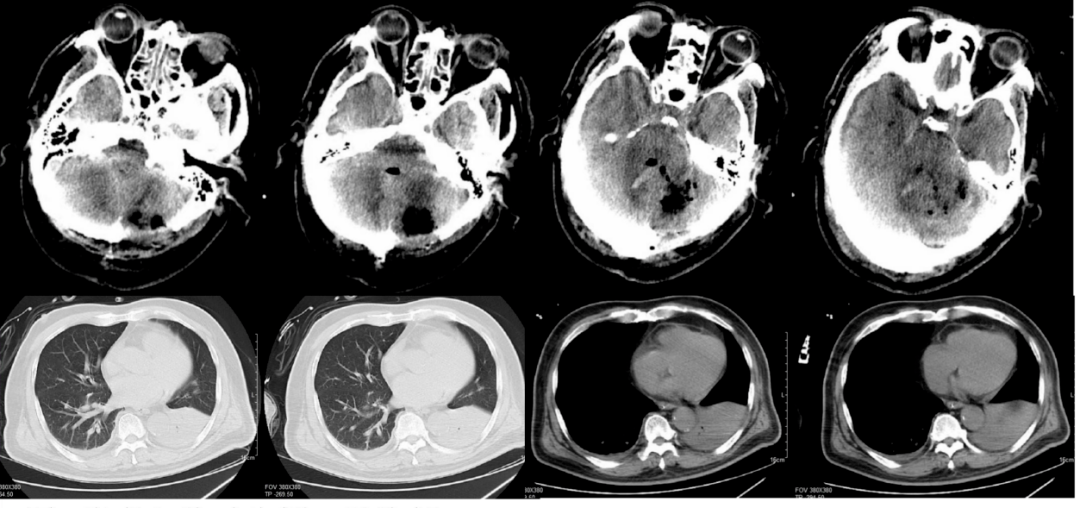

图1.患者入院时头颅及胸部ct.

以上为头颅ct检查结果,患者右侧中,后颅凹可见巨大肿物占位影.